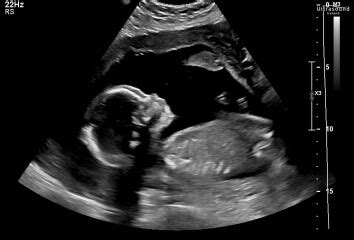

20-Week Scan in South Africa: Common Concerns Explained# Navigating Your 20-Week Scan Journey: What to ExpectAlright, guys, let’s chat about one of the most anticipated and, let’s be honest, nerve-wracking milestones in any pregnancy: the 20-week anatomy scan . For many expectant parents, especially here in South Africa , this isn’t just another check-up; it’s often the first really detailed look at your little one, a chance to see their tiny fingers and toes, and maybe even find out if you’re having a boy or a girl! But beyond the excitement, there’s also a common undercurrent of anxiety. We’ve all heard stories, or maybe just had those what if thoughts swirling in our heads: What if they find something? What if it’s “bad news”? It’s totally normal to feel this way. The truth is, the 20-week scan, also known as the mid-pregnancy anatomy scan or anomaly scan , is a crucial diagnostic tool designed to thoroughly examine your baby’s development. It’s a comprehensive look at almost every part of your little human, from the top of their head to the tips of their toes, ensuring everything is growing as it should be. The primary goal is to check for any significant structural abnormalities or congenital anomalies that might affect your baby’s health or require specialized care after birth. It’s a proactive step in your prenatal care journey, giving your healthcare team vital information to plan for the safest possible delivery and subsequent care. While the thought of receiving “bad news” is terrifying, remember that the vast majority of these scans reveal healthy, developing babies. Even when common concerns during a 20-week scan in South Africa are identified, they are often minor, easily managed, or even resolve on their own, rather than indicating a serious problem. Our aim today is to demystify this important scan, help you understand what it entails, and equip you with the knowledge to navigate any findings with confidence and clarity, minimizing unnecessary worry and focusing on the joyous journey ahead. This scan is a beautiful opportunity to connect with your baby and gain reassurance, but also to be prepared, should any unexpected findings come to light. We’ll explore what those common findings might be and what they really mean for you and your little one, all within the context of healthcare and support systems available right here in South Africa. So, take a deep breath, grab a cup of tea, and let’s dive in. # Understanding the Nitty-Gritty: What Sonographers Look ForOkay, so you’re lying there, tummy exposed, jelly applied, and the sonographer is quietly moving the transducer around, their eyes glued to the screen. You might be wondering, what exactly are they looking for during this incredibly detailed examination? Well, guys, this isn’t just a quick peek; it’s a meticulously structured assessment of your baby’s entire anatomy, and it’s designed to be as thorough as possible. The 20-week scan in South Africa (and globally, for that matter) systematically checks a whole laundry list of things. First off, they’re measuring your baby to ensure they’re growing appropriately. This includes head circumference, abdominal circumference, and femur length – all crucial indicators of healthy development. Beyond measurements, they delve deep into organ systems. The brain is carefully examined for its structure, including the ventricles (fluid-filled spaces) and the cerebellum, to ensure there are no signs of conditions like hydrocephalus or anencephaly. The heart , a tiny but mighty organ, gets an incredibly detailed assessment. Sonographers look at the four chambers, the great vessels (aorta and pulmonary artery), and the rhythm, checking for congenital heart defects which, while sometimes serious, can often be managed. Moving down, the spine is viewed in both longitudinal and transverse sections to rule out spina bifida or other vertebral anomalies. The face is examined for conditions like cleft lip or palate. Then there are the limbs – all four of them! They count fingers and toes (sometimes a tricky task!), assess the long bones, and check for any clubfoot or other skeletal issues. The internal organs also get their moment in the spotlight: the stomach should be visible, indicating the baby is swallowing amniotic fluid; the kidneys are checked for size and any blockages (like hydronephrosis or renal pyelectasis ); and the bladder should fill and empty. The abdominal wall is also scrutinized to ensure all organs are safely inside. Don’t forget the supporting cast: the placenta is assessed for its position (e.g., to rule out placenta previa , which might mean a C-section), and the amniotic fluid volume is measured, as too little (oligohydramnios) or too much (polyhydramnios) can indicate issues. Even the umbilical cord is checked to ensure it has the usual three vessels – two arteries and one vein – though sometimes a single umbilical artery (SUA) is found, which we’ll discuss later. Each of these checks is vital, providing a comprehensive picture of your baby’s health. It’s important to understand that while they’re looking for potential problems, they’re also verifying the normal, beautiful development of your baby. Finding a variation doesn’t automatically mean “bad news”; often, it’s just something to monitor, and that’s precisely why this scan is so invaluable for parents-to-be across South Africa . This deep dive helps prepare your medical team for any necessary interventions, ensuring your baby gets the best possible start in life. # Common Findings That Aren’t Always “Bad News” (and When They Might Be)Alright, so you’ve just had your scan, and maybe the sonographer or doctor mentioned a specific “finding.” Cue the instant Google search, the racing heart, and the assumption that it’s bad news . Hold up, guys! One of the most important things to understand about the 20-week scan in South Africa is that sometimes, something is noted that, while requiring attention, isn’t necessarily a cause for major alarm. These are what we call soft markers or common variations that often resolve or are completely benign. Let’s delve into some of these common concerns during a 20-week scan in South Africa that often lead to undue stress, and clarify when they might actually be something to watch.First up, Choroid Plexus Cysts (CPCs) . These are small fluid-filled sacs within the choroid plexus of the brain, which is tissue responsible for producing cerebrospinal fluid. Finding a CPC can be incredibly unsettling, as it’s sometimes associated with an increased risk of Trisomy 18 (Edwards Syndrome). However, here’s the crucial part: in isolated cases (meaning no other abnormalities are found), CPCs are present in about 1-2% of normal pregnancies and almost always disappear on their own by 28 weeks. If your baby has an isolated CPC, with no other markers or risk factors, the chance of Trisomy 18 is extremely low, often similar to that of the general population. Your doctor might recommend follow-up scans or offer genetic counseling, but don’t panic immediately; often, it’s just a transient finding.Next, Echogenic Bowel . This is when your baby’s bowel appears brighter than usual on the ultrasound, similar in brightness to bone. It can sometimes be a marker for cystic fibrosis , chromosomal abnormalities (like Down Syndrome), intrauterine growth restriction (IUGR) , or intra-amniotic bleeding . Again, though, it can also be a normal variation. If an echogenic bowel is found, especially if it’s moderate to severe, your healthcare provider will likely recommend further testing, such as genetic screening for cystic fibrosis, a detailed scan for other abnormalities, and potentially monitoring for IUGR. But in many cases, particularly if it’s mild and isolated, it can resolve without any underlying pathology. It’s about looking at the whole picture , not just one isolated finding.Then there’s Single Umbilical Artery (SUA) . Usually, the umbilical cord has two arteries and one vein. An SUA means there’s only one artery and one vein. While SUA can sometimes be associated with kidney abnormalities , heart defects , or chromosomal issues , in about 75% of cases, it’s an isolated finding in an otherwise healthy baby. If an SUA is detected, your doctor will likely perform a more detailed scan of your baby’s heart and kidneys to ensure no other anomalies are present. If all other structures are normal, the prognosis is generally excellent, although some babies with SUA might be at a slightly increased risk of intrauterine growth restriction , so often closer growth monitoring is recommended. Mild Ventriculomegaly refers to a slight enlargement of the fluid-filled spaces (ventricles) in the baby’s brain. This is another one that can cause significant anxiety because moderate to severe ventriculomegaly can indicate serious neurological issues. However, mild ventriculomegaly (usually defined as a ventricular width between 10mm and 12-15mm) is often benign, especially if it’s isolated. It can resolve spontaneously, remain stable, or rarely, progress. If detected, you’ll likely be referred to a fetal medicine specialist for a higher-level ultrasound and potentially an MRI of the fetal brain. Genetic counseling and chromosomal analysis might also be offered. But remember, a mild finding has a much better prognosis than a severe one, and many babies with isolated mild ventriculomegaly develop completely normally.Finally, Renal Pyelectasis (Kidney Pelvis Dilation) . This is when the collecting system of one or both of your baby’s kidneys appears slightly dilated. It’s quite common, affecting about 1-2% of pregnancies, and more often seen in boys. While severe pyelectasis can indicate a blockage or reflux requiring postnatal surgery, mild pyelectasis often resolves spontaneously during pregnancy or shortly after birth. It can also be a soft marker for Down Syndrome , but usually only when other markers are also present. If pyelectasis is found, your doctor will monitor it with follow-up ultrasounds during pregnancy and likely recommend a postnatal ultrasound for your baby to confirm resolution or assess if any intervention is needed. Most of the time, this is a minor issue that simply requires monitoring.The takeaway here, folks, is that a “finding” on your scan doesn’t automatically equate to a devastating diagnosis. These common concerns are often just that – concerns that warrant further investigation, but frequently turn out to be minor, manageable, or even resolve on their own. The key is clear communication with your healthcare provider in South Africa , understanding the specific implications of the finding, and following through with any recommended follow-up tests or consultations. Don’t let a single mention throw you into a spiral of despair; gather the facts, ask all your questions, and trust in your medical team to guide you through. # When “Bad News” Does Arise: Serious Conditions and Support in South AfricaWhile we’ve just discussed how many common concerns during a 20-week scan in South Africa turn out to be manageable or even benign, it’s also important to acknowledge that sometimes, the 20-week anatomy scan can indeed reveal more serious conditions. This is the “bad news” part that every expectant parent dreads, and it’s a moment that can be incredibly distressing, overwhelming, and heartbreaking. Learning that your baby has a significant health challenge, a severe congenital anomaly, or a condition incompatible with life is a profound shock. It can feel like your world has been turned upside down in an instant, and it’s absolutely okay to feel a maelstrom of emotions – grief, anger, confusion, sadness, and fear. While the examples of truly serious conditions are vast, they might include major cardiac defects that would require multiple surgeries, severe neural tube defects like large open spina bifida or anencephaly, major chromosomal abnormalities with significant health implications, or other complex genetic syndromes . In some very rare and tragic instances, the scan might detect conditions that are considered lethal , meaning the baby cannot survive outside the womb for long, if at all.When such difficult news is delivered, it’s not just a medical diagnosis; it’s a deeply personal and emotional crisis. The first step, and often the most crucial, is to seek a clear and comprehensive diagnosis . Your healthcare provider in South Africa will typically refer you to a fetal medicine specialist – an obstetrician who specializes in high-risk pregnancies and fetal abnormalities. This specialist will conduct higher-level ultrasounds, potentially fetal echocardiograms (detailed heart scans), or even an MRI to get the clearest possible picture of your baby’s condition. You might also be offered invasive diagnostic tests like amniocentesis or chorionic villus sampling (CVS) to confirm chromosomal or genetic conditions, which can provide definitive answers where ultrasound alone might not. These tests carry a small risk, but the information they provide is invaluable for decision-making.Understanding the diagnosis is paramount because it informs your options. You will need to have frank and honest discussions with your medical team about the prognosis, potential treatments, the quality of life your child might have, and the long-term care required. This is an incredibly challenging time for any family, and the support network available to you is vital. In South Africa , you will find that a multidisciplinary team often rallies around families facing these diagnoses. This team can include not just your obstetrician and fetal medicine specialist, but also genetic counselors who can explain the condition, its inheritance patterns, and recurrence risks. Pediatric specialists, such as pediatric cardiologists , neurosurgeons , or neonatologists , might be brought in to discuss the specific care your baby would need after birth. Importantly, there are also psychologists and counselors who specialize in perinatal bereavement and grief, offering crucial emotional support for you and your partner as you navigate these difficult choices and feelings. Support groups, both formal and informal, can also be a lifeline, connecting you with other parents who have walked a similar path. Sharing experiences and finding solidarity can provide immense comfort during a time of isolation.Making decisions about continuing the pregnancy, pursuing palliative care, or, in very tragic circumstances, considering termination, are deeply personal and ethically complex choices that only you and your partner can make. Your medical team’s role is to provide you with all the factual information, support your emotional well-being, and respect your decisions without judgment. It’s a journey no one wishes to embark on, but know that resources and compassionate care are available in South Africa to help you through. The goal, even in the face of “bad news,” is to ensure you feel supported, informed, and empowered to make the best decisions for your family, always prioritizing your baby’s well-being and your own emotional health. Remember, you are not alone in this; there are dedicated professionals and communities ready to offer a helping hand when your 20-week scan takes an unexpected turn. # Your Role and Next Steps: Advocating for Your Pregnancy JourneyWhen faced with any finding, whether a common concern or truly bad news during your 20-week scan in South Africa , your role as an expectant parent shifts from passive recipient to active advocate. This is your pregnancy journey, and your engagement is absolutely crucial for navigating any subsequent steps effectively. The key to moving forward with confidence and clarity, regardless of the scan’s outcome, lies in proactive communication and informed decision-making. Don’t ever hesitate to ask questions – and lots of them! Write them down before your appointment if you need to. Clarify anything you don’t understand about the findings, the diagnosis, the prognosis, and the recommended next steps. Ask about the likelihood of the finding resolving, the potential risks, and what specific interventions might be required. Understanding the why behind every recommendation will empower you.Another critical step is to consider getting a second opinion , especially if the findings are complex, serious, or if you feel uncertain about the information you’ve received. In South Africa , seeking a second opinion from another fetal medicine specialist or an expert in a particular field (e.g., pediatric cardiology if a heart defect is suspected) is a common and often recommended practice. Different specialists may offer slightly different perspectives or confirm a diagnosis, providing you with more peace of mind or additional options. This isn’t about distrusting your initial doctor; it’s about gathering all the information and perspectives necessary to make the best possible decisions for your baby and your family. Understanding all available test results is also paramount. If genetic tests are offered, make sure you understand what they are screening for, the accuracy rates, and what a positive or negative result would truly mean. Don’t be afraid to ask for copies of your reports and to have your doctors explain them in layman’s terms.Beyond diagnosis, think about the follow-up scans and appointments . These are often essential for monitoring the progression of any finding, assessing the baby’s growth, and preparing for delivery. Adhering to these schedules is vital. For some conditions, lifestyle considerations might be discussed, although for most congenital anomalies, maternal lifestyle changes during pregnancy do not alter the condition. However, maintaining a healthy lifestyle – balanced nutrition, appropriate exercise, and avoiding harmful substances – remains important for overall pregnancy health. The most powerful tool you have is communication with your healthcare providers . Build a relationship of trust and openness with your obstetrician, midwives, and any specialists you see. They are your guides through this process. Keep them informed of your concerns, your research, and your emotional state.Finally, think about resources available in South Africa . Many hospitals have social workers or patient navigators who can help you access support services, financial aid (if applicable), or connect you with local support groups. Organizations dedicated to specific conditions (e.g., Down Syndrome Association, Heart & Stroke Foundation) often have local chapters or networks that can provide invaluable practical and emotional support, connecting you with families who understand your journey. Remember, advocating for your pregnancy journey isn’t just about managing medical findings; it’s about protecting your emotional well-being, ensuring you have all the information, and building a robust support system around you. Embrace your strength, trust your instincts, and know that you are doing everything you can to provide the best possible start for your little one, even when the path forward seems challenging. # Embracing Your Journey with Knowledge and HopeSo, as we wrap up our chat about the 20-week scan in South Africa and the common concerns that might pop up, let’s bring it back to a place of hope and empowerment. We’ve explored the excitement and the anxiety that comes with this significant milestone, delved into the incredible detail that sonographers look for, unpacked those common findings that aren’t always “bad news” , and bravely confronted what it means when truly serious conditions are diagnosed. Remember, guys, the purpose of this detailed scan isn’t to scare you; it’s to inform you. It’s a testament to the advancements in modern medicine that we can learn so much about our babies before they even arrive, allowing for proactive planning and, if necessary, early intervention. The 20-week anatomy scan is a powerful tool in your prenatal care, providing invaluable insights into your baby’s development and offering the chance to address any potential issues head-on.The journey of pregnancy is, by its very nature, a roller coaster of emotions. There will be moments of pure joy, unadulterated excitement, and profound love, alongside periods of worry, uncertainty, and sometimes, even profound sadness. What’s crucial is how you navigate these moments, armed with knowledge and surrounded by support. When those common concerns during a 20-week scan in South Africa are flagged, remember that the initial finding is often just the beginning of a conversation, not the end of the world. Most of these “soft markers” resolve or are benign, simply requiring a closer look. And even in the rare instances of truly “bad news,” there is a robust network of dedicated healthcare professionals, specialists, counselors, and support groups available in South Africa to guide you every step of the way. You are not alone.Embrace your journey with an open mind and a strong heart. Trust in your medical team, ask all your questions, advocate for your needs, and seek out the support that resonates with you. Whether your scan is perfectly normal (as most are!), or if it brings some unexpected news, remember that every step is part of your unique story with your baby. Focus on the love, the connection, and the incredible miracle that is growing within you. This phase of pregnancy is about celebrating life, preparing for parenthood, and facing the future with resilience. Let the knowledge you’ve gained today empower you to navigate any outcome with courage, ensuring the best possible path forward for you and your precious little one. You’ve got this!